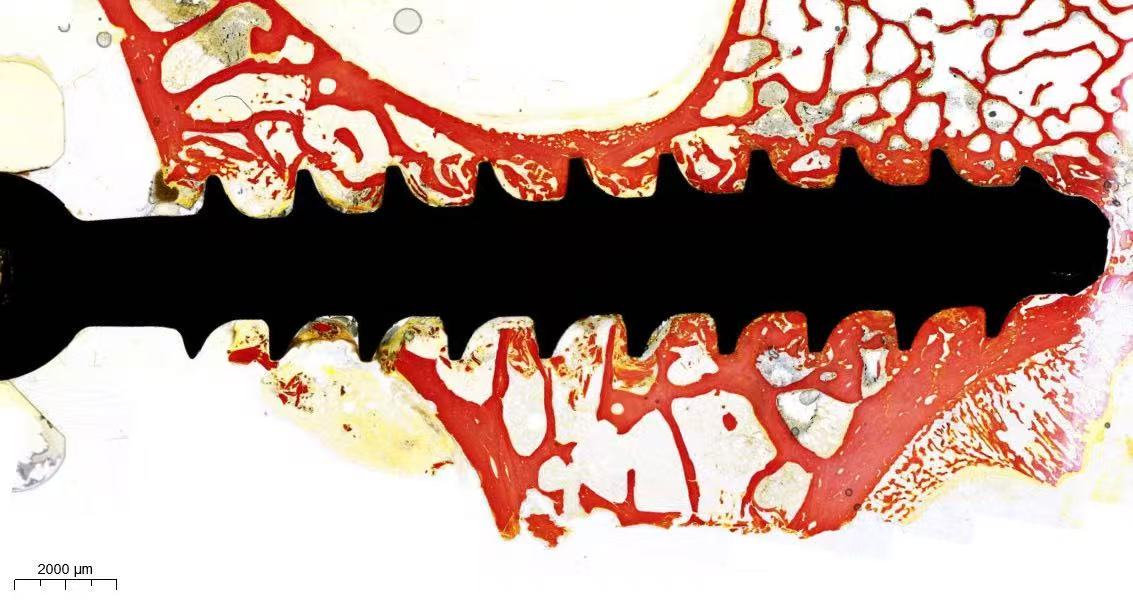

大动物骨组织样本很难通过脱钙、石蜡切片等方式进行制片。制片前的脱钙时间非常长,且长时间脱钙会影响染色效果。可将此类硬度较高的样本不经脱钙直接进行梯度酒精脱水7200树脂包埋成硬度很高且环保无任何气泡的树脂块,结合后续的硬组织切片机配合磨片机对树脂块进行切片成20μm左右的切片再进行后续染色

带金属植体的骨组织或者带金属植体的其他组织(皮肤、心脏,血管)以及带骨水泥,高分子硬材料的组织还有大动物的骨组织,各种牙齿等高硬度的样本基本无法通过脱钙、软化石蜡切片等方式进行制片。可将此类硬度较高的样本不经脱钙直接进行梯度酒精脱水7200树脂包埋成硬度很高且环保无任何气泡的树脂块,结合后续切磨系统将树脂块通过切片磨片制备成20μm左右薄而均匀的树脂片,再进行后续染色

以上不同类型的硬组织不经脱钙软化处理的树脂包埋切片能够最大限度地保持组织和材料原有结构和形态,不影响后期的染色和结构观察分析。

树脂包埋好的样本,通过先切后磨(打磨抛光)的方式,将样本制成20-30um左右的树脂切片

切磨片用树脂载片进行制片,整张切片厚约1.6mm,无法用普通的切片扫描仪扫描成像,推荐使用匈牙利的3D扫描仪进行切磨片的扫描全景成像,全景观察组织结构,图像更清晰,分辨率对比度更高。